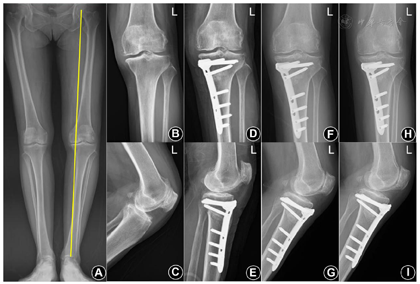

于术后第1天、术后1、3、6、12、18和24个月及此后每年进行随访。18例患者均接受了随访,随访时间为1个月至2年。于随访的X线片上测量FTA、胫骨近端内侧角(medial proximal tibial angle, MPTA)和胫骨平台后倾角(posterior slope angle, PSA),结果见表1。术后患膝疼痛减轻;内侧胫股关节间隙变宽,FTA变小,下肢力线得以纠正,典型病例见图1。

入院后完善术前常规检查;全下肢负重正位力线片与膝关节正侧位X线片示:内侧胫股关节间隙变窄,伴有胫骨平台软骨下骨质致密及关节缘骨质增生;膝内翻畸形,18例患者的股胫角(femorotibial angle, FTA)为(187.94±1.62)°。

排除禁忌证后行内侧开放楔形胫骨高位截骨术。从鹅足前缘向后上方做一切口,至胫骨平台的后内侧角处。分离皮下组织后,将两根克氏针打入胫骨以指示截骨方向。使用摆锯于克氏针下方进行横断面截骨,于胫骨结节近端进行冠状面截骨。插入骨凿逐渐撑开截骨面,18例(19膝)患者撑开宽度为(12.8±2.2)mm。置入TomoFix钢板并用螺钉固定。C臂机透视内固定在位牢固,冲洗后逐层闭合切口,留置引流。